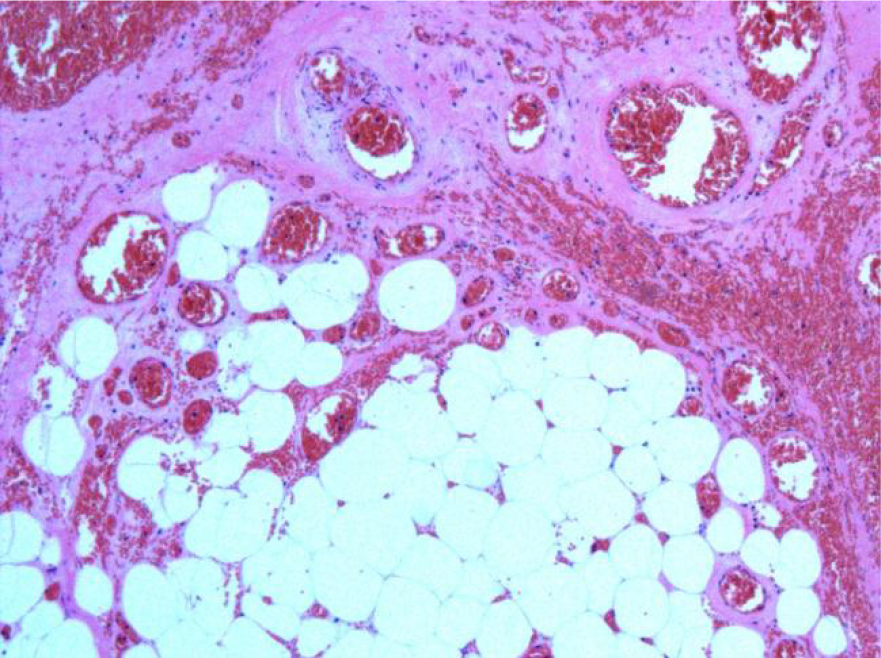

The patient underwent emergency laparoscopy under general anesthesia. The procedure revealed 50 mL of dark-red bloody ascites in the pelvis and twisting of the right omentum along its longitudinal axis, with a 10 cm × 8 cm purple-black necrosis at the distal end (Figure 2). No cysts or tumors were found. The umbilical port was extended to 4 cm to exteriorize the right-sided omentum, which was found to be twisted clockwise by 1980 degrees (Figure 3). Ligation was performed at 2 cm above the torsion site, and the necrotic portion was resected. A pathological examination revealed omental hemorrhage, degeneration, and necrosis, along with vascular embolism and peripheral acute inflammatory cell infiltration (Figure 4).